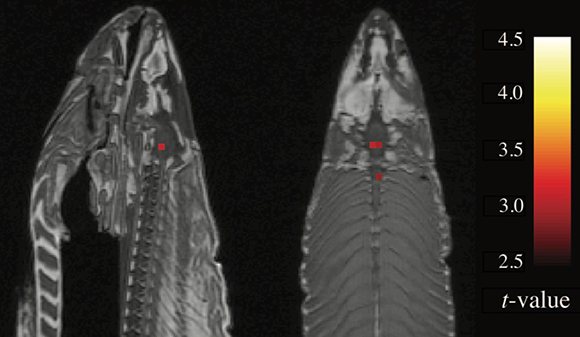

كانت لدى بينيت فكرة – اقترح استخراج البيانات من سمك السّلمون المجمد، الّذي كان يحتوي على حوالي 65 ألف ڤوكسل، والبحث عن ڤوكسلات نَشِطة. في حال عُثر على مثل وحدات الڤوكسل هذه في سمكة ميّتة، فإنّ ذلك من شأنه أن يمثّل بوضوح وجود خطأ من النّوع الأوّل في الاختبار، وأهمّيّة إيجاد تصحيح للمقارنات المتعدّدة. ما كان يتوقّعه بينيت هو وجود توزيع عشوائيّ لوحدات ڤوكسل فرديّة، ولكن ولشدّة دهشته، فقد رأى ثلاث مجموعات واضحة من وحدات ڤوكسل النشطة – وهو نمط من النّشاط لا ينبغي على الإطلاق العثور عليه في دماغ سمك السّلمون المجمَّد السّاكن.

سارع بينيت إلى تقديم نتائجه في مؤتمر دوليّ مهمّ عُقِد في ذلك العام، بعد أن أقنع منظمّيه بأنّها ليست خُدعة. أثارت الدّراسة ردود أفعال كثيرة – كان هناك من اعتبرها خدعة غبيّة، وآخرون قالوا إنّ خطأً قد حدث في عمليّة تحليل البيانات. أدرك بينيت أنّه على الرّغم من الخوف مما قد تسبّبه دراسةٌ غبيّة على سمكة ميّتة من تأثيرٍ سيّء على سمعتِه كعالم في بداية طريقه، إلّا أنّ في يديه نتائج لا بدّ من نشرها. في عام 2009، نشر بينيت وزملاؤه نتائج فحص الـ fMRI للسّلمون. أثارت المقالة نقاشات صاخبة في مجتمع البحث العالميّ، بل وحاز مؤلّفوها على جائزة إيغ نوبل (نوبل للحماقة العلميّة) في عام 2012.

لقد فوجئ بينيت عندما رأى ثلاث مجموعات واضحة من وحدات الڤوكسل النشطة – وهو نمط من النشاط لا ينبغي العثور عليه في دماغ سمك السّلمون المجمّد. مسح الـ MRI للسّمكة الميّتة | Bennett, C. et al. JSUR (2010)، CC BY 3.0